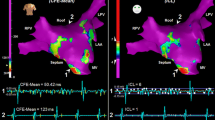

The resultant LA maps based on the three consecutive AEG segments with 2.5-s duration each for one patient as measured by the ICL (upper), the ACI (middle), and the SCI (bottom). The location of the AEGs classified as stable CFAE, stable non-CFAE, and unstable shown in Fig. 2 are marked in the ICL map

AEG classifications were more similar between AEGs with 5- and 8-s durations, as shown in Table 3. The Spearman’s correlation was higher for 5 versus 8 s for ICL, ACI, and SCI, than 2.5 versus 5 s and 2.5 versus 8 s. Although the agreement of CFAE classification also deteriorated with higher ICL thresholds, the kappa score suggests higher agreement in the CFAE classification performed by 5- and 8-s segments in all cases. Figure 6 shows an example of the resulting CFAE map for ICL, ACI, and SCI measured with AEG durations. Maps for the remaining patients are provided in the Supplementary material.